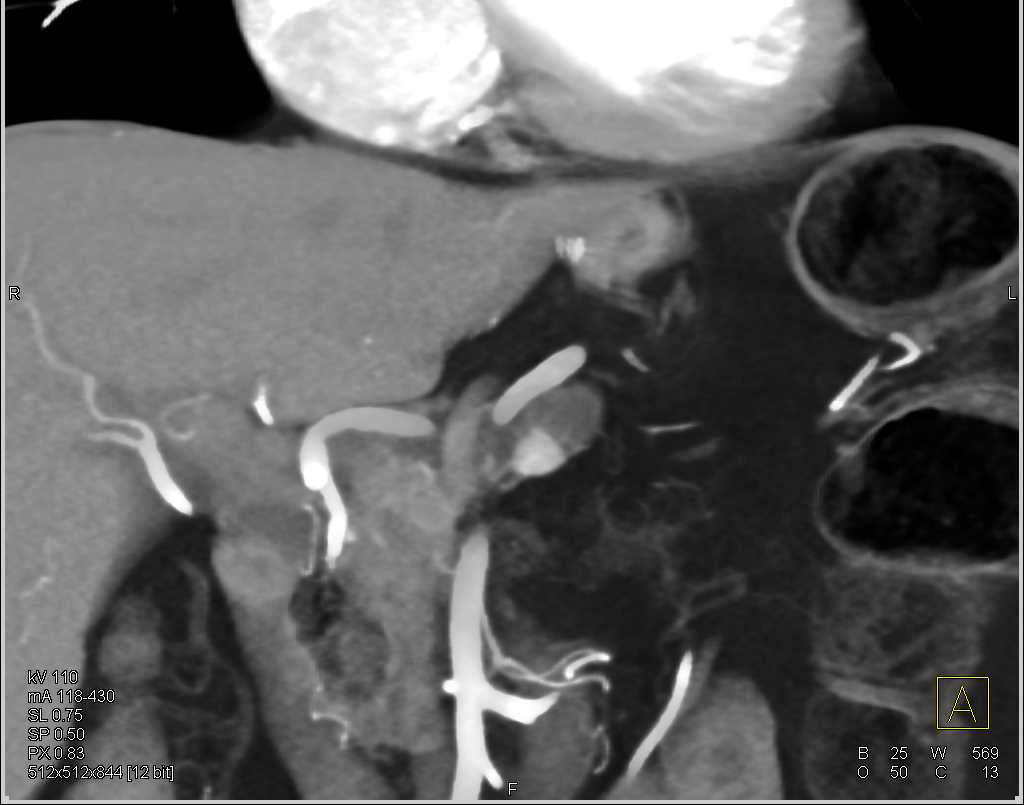

Aortic Aneurysm Repair with Large Endoleak